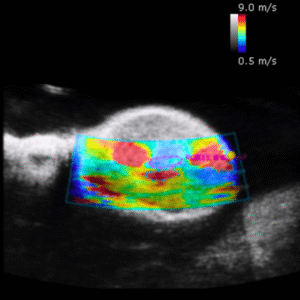

Shear wave Elastography PT2